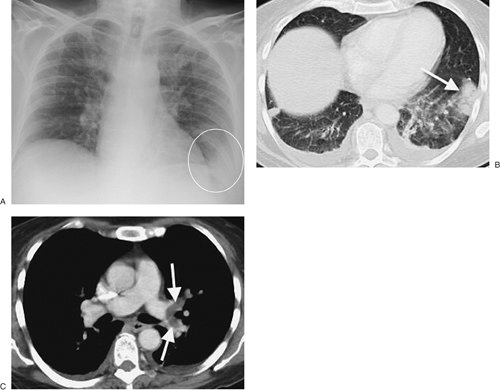

Pulmonary infarction results in airspace opacities that are usually multifocal and predominantly in the lower lungs. They usually appear within 12 to 24 hours after the embolic event. The opacities are classically peripheral, with a triangular or rounded shape (thus the term "Hampton hump"), and they are always in contact with the pleural surfaces (Fig. 12-8). The apex or hump of the opacity is directed toward the lung hilum. Occasionally, lobar consolidation resembling pneumonia can occur. Air bronchograms are rarely present. It is important to

P.212

note that the opacities can be a result of a combination of atelectasis and pulmonary hemorrhage without infarction, in which case clearing occurs within a week. Infarction takes several months to resolve, often with residual scarring (Fig. 12-9). As infarcts resolve, they melt away "like an ice cube" (giving rise to the melting ice cube sign; see Fig. 2-16). The opacity clears from the periphery first, whereas in pneumonia the opacity clears homogeneously (both centrally and peripherally) at the same time. Cavitation can occur within infarcts but is rare without coexisting infection, either secondary infection of an infarct or a result of septic emboli or vasculitis. Pleural effusions related to pulmonary emboli are usually small, unilateral, and associated with pulmonary infarction.

FIGURE 12-8. Pulmonary infarct. A: PA chest radiograph of a 52-year-old woman with acute pulmonary embolism shows focal airspace disease at the left costophrenic angle (circle). B: CT shows bilateral subpleural airspace opacities, which are largest in the left lower lobe (arrow), and bilateral pleural effusions. C: CT with mediastinal windowing confirms the presence of a central filling defect (arrows) within otherwise opacified lingular and left lower lobe pulmonary arteries, characteristic features of acute pulmonary emboli.